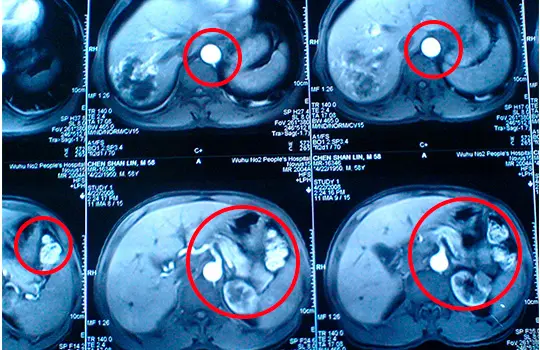

Above: A 68-year-old woman with a 10-year history of liver dysfunction. Previous tests showed significant metabolic decline and toxin buildup, indicating impaired liver function.

Above: The patient's tests after using the Yoofibre show significant improvement in liver function, with detoxification and metabolic health greatly enhanced, approaching the levels of a healthy liver.